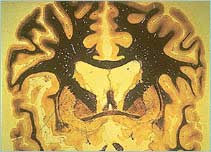

Section through the brain

Coronal section through a human brain showing the thalamus and caudate nucleus. Courtesy of University of Wisconsin, Dept. of Anatomy

The orbital-frontal cortex (OFC) is the part of the brain that notices when something is wrong. For example, when the OFC registers that there is dirt nearby, it sends a 'worry' signal to the thalamus.

The thalamus directs signals from many parts of the brain to places that can interpret them - in this case back to the OFC. These nerve cell connections form a loop in the brain. The caudate nucleus lies between the OFC and the thalamus and regulates signals sent between them.